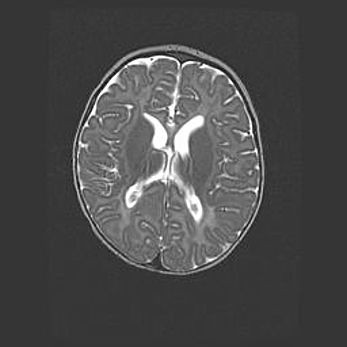

Церебральная ишемия II.

Возраст: 5 дней

Вес: 3400 г

Пол: женский

Окружность головы: 35 см

Срок гестации: 39 недель

Церебральная ишемия – это заболевание, характеризующееся недостаточностью (гипоксией) либо полным прекращением (аноксией) снабжения мозга кислородом по причине закупорки одного или нескольких сосудов. Это приводит к  что метаболическим расстройствам различной степени тяжести в тканях головного мозга, развитию коагуляционных некрозов и гибели нейронов.